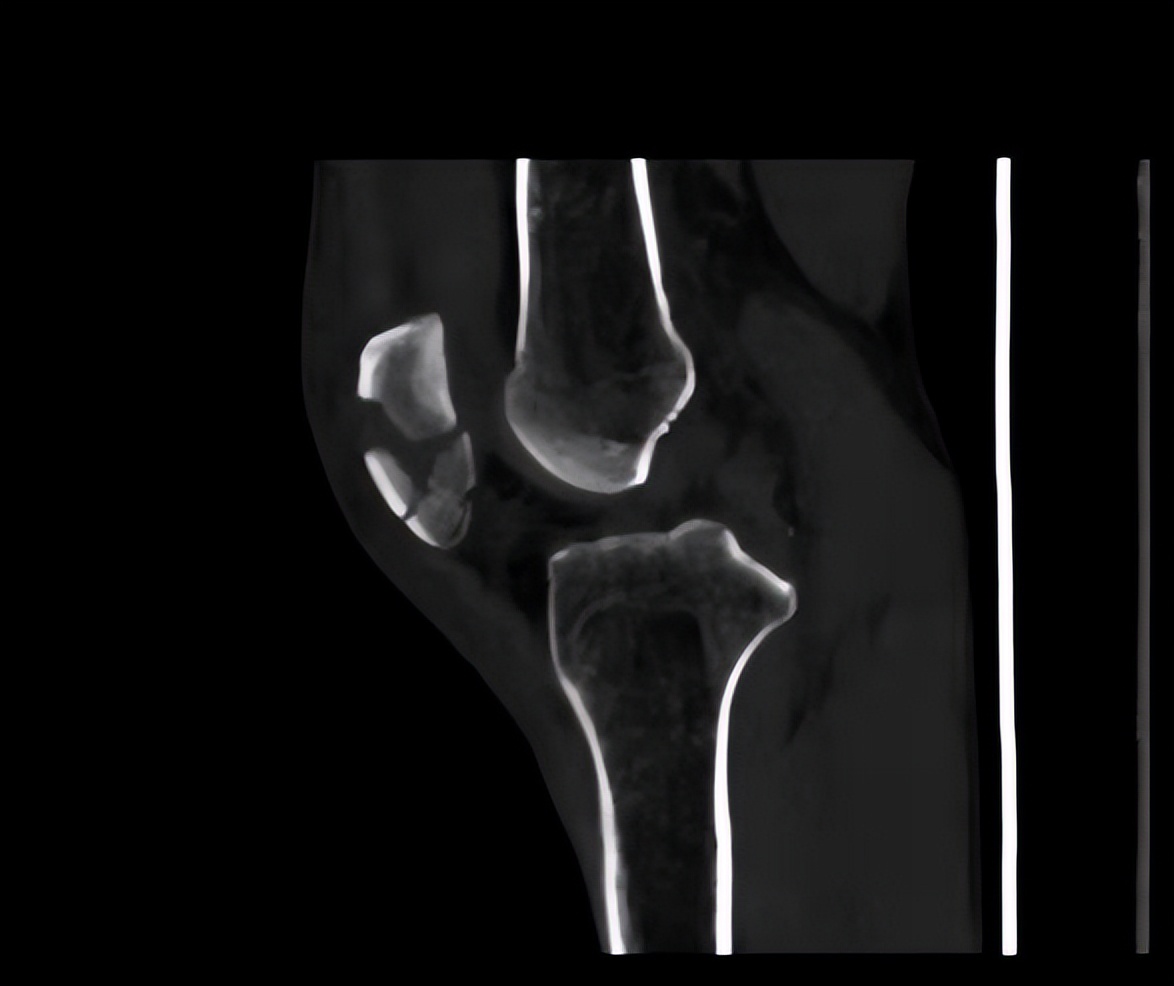

患者入院后,基于“左髌骨骨折”的考虑,进一步完善CT检查,MRI检查,心电图检查,血常规,血凝全套以及血型检测,肝功和肾功等相关检查。这些检查是为了给患者行手术治疗做准备。检查结果示患者左髌骨粉碎性骨折,股骨内侧髁水肿,关节积液,膝关节周围软组织损伤,内侧半月板后角和体部损伤;窦性心律正常范围;中性粒细胞百分比增加,血凝D二聚体增多,0.93微克每升,总胆红素增多,直接胆红素增多。

基于上述检查结果,考虑患者左髌骨骨折,结合患者具体疾病发生情况,可以临床诊断为左髌骨骨折,遂予以患者手术治疗,行左髌骨骨折切开复位内固定术,时长2~3小时。术后给予头孢类消炎药及克拉霉素进行抗炎消菌,避免手术后感染,对皮肤破损处使用碘伏消毒,保持皮肤破损处清洁干燥。手术后给予患者补液治疗,维持身体稳态和手术后的身体虚弱。

经住院治疗半个多月,患者左膝伤口愈合良好,左膝关节可轻微活动,足趾感觉运动良好,末梢血运正常。复查X片提示髌骨愈合良好,断端复位佳,血常规检查已恢复正常。对患者进行日常生活活动评定,患者大部分日常生活活动可以自理,遂予以出院。